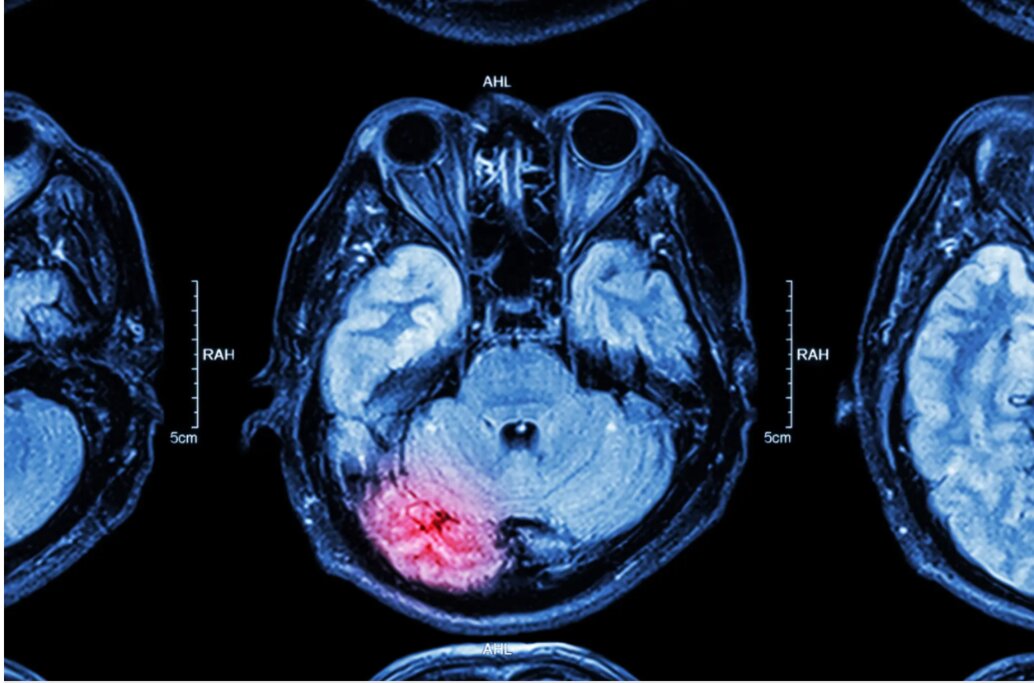

Old  Default Đột quỵ gia tăng ở người trẻ: "Cảnh báo đỏ" độ tuổi 20 - 40

Từng là căn bệnh gắn liền với người cao tuổi, đột quỵ giờ đây đang "tấn công" ngày càng nhiều người trong độ tuổi thanh niên và trung niên.

Theo dữ liệu từ Trung tâm Kiểm soát và Pḥng ngừa Dịch bệnh Hoa Kỳ (CDC), số ca đột quỵ ở nhóm tuổi từ 18–44 đă tăng tới 14,6% chỉ trong ṿng 2 năm (2020–2022). Điều này đang khiến các chuyên gia y tế đau đầu, đặc biệt khi ngày càng nhiều người trẻ hoàn toàn khỏe mạnh, không có tiền sử bệnh nền, vẫn bị đột quỵ một cách bất ngờ

Các xét nghiệm sau đó cho thấy cơn đột quỵ đến từ t́nh trạng tắc mạch, nghĩa là cục máu đông h́nh thành ở nơi khác trong cơ thể và trôi lên năo. Đáng chú ư, cả hai bệnh nhân đều sử dụng thuốc tránh thai đường uống - một yếu tố được biết là có thể làm tăng nguy cơ h́nh thành huyết khối.